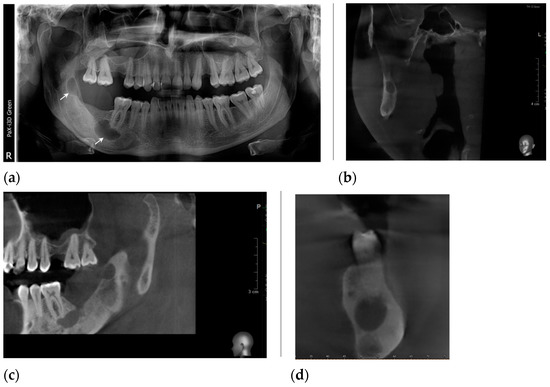

2. Case Presentation